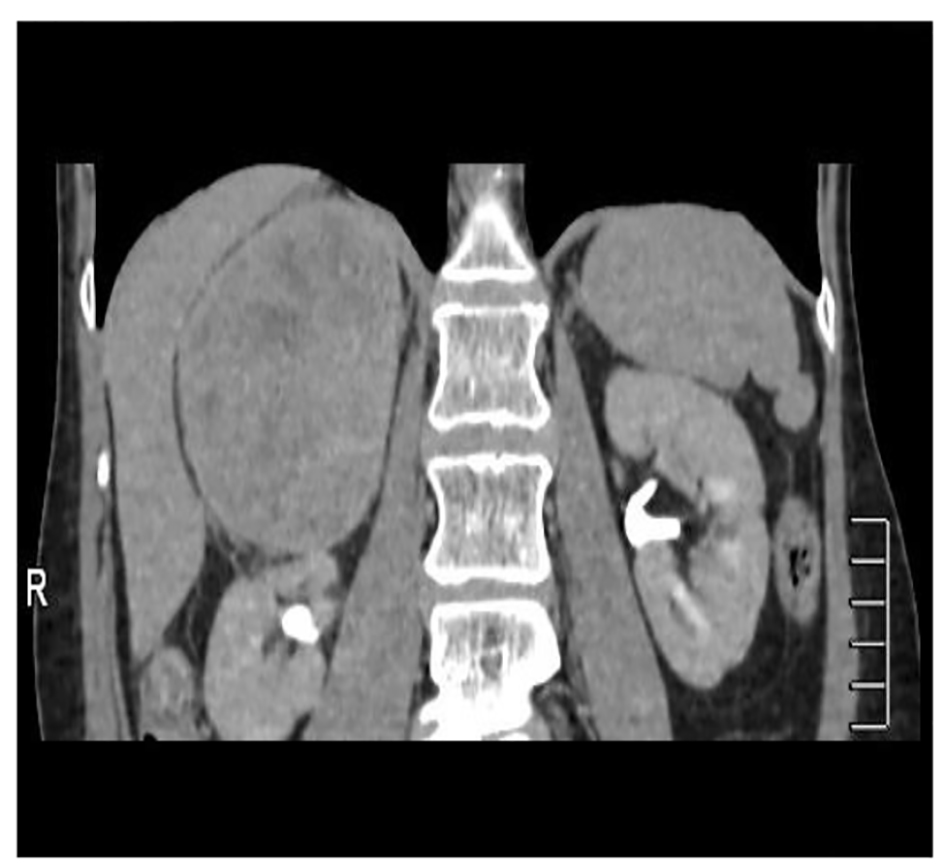

A 56-year-old woman smoker was dispatched to the hematology department with thrombocytopenia after a routine health examination. Physical examination was normal. The patient presented a right flank disturbance. CT showed a right homogeneous adrenal mass of 10.8 cm diameter (Fig. 2). Laboratory tests with catecholamines and tumor marks were negative. Therefore, a functioning tumor was discarded.

![]() Click for large image | Figure 2. Abdominal CT showing an adrenal lesion. |

The patient underwent a right adrenalectomy laparoscopic surgery. Pathological evaluation revealed an adrenal schwannoma. Macroscopically tumor was well-circumscribed and encapsulated. The tumor measured 10 × 9.5 × 6 cm and weighed 427 g (Fig. 3). Histopathological findings showed regular fusiform cells, without atypia or mitosis and fibrillar cytoplasm. Intersecting cells were surrounded by histiocytes. Also there was collagen area which was stained with Masson’s trichrome (Fig. 4). Tumor cells expressed S-100 (Fig. 5), IV collagen, vimentin and GFAP. The desmin and c-kit were negative. Ki67 activity was 30%.